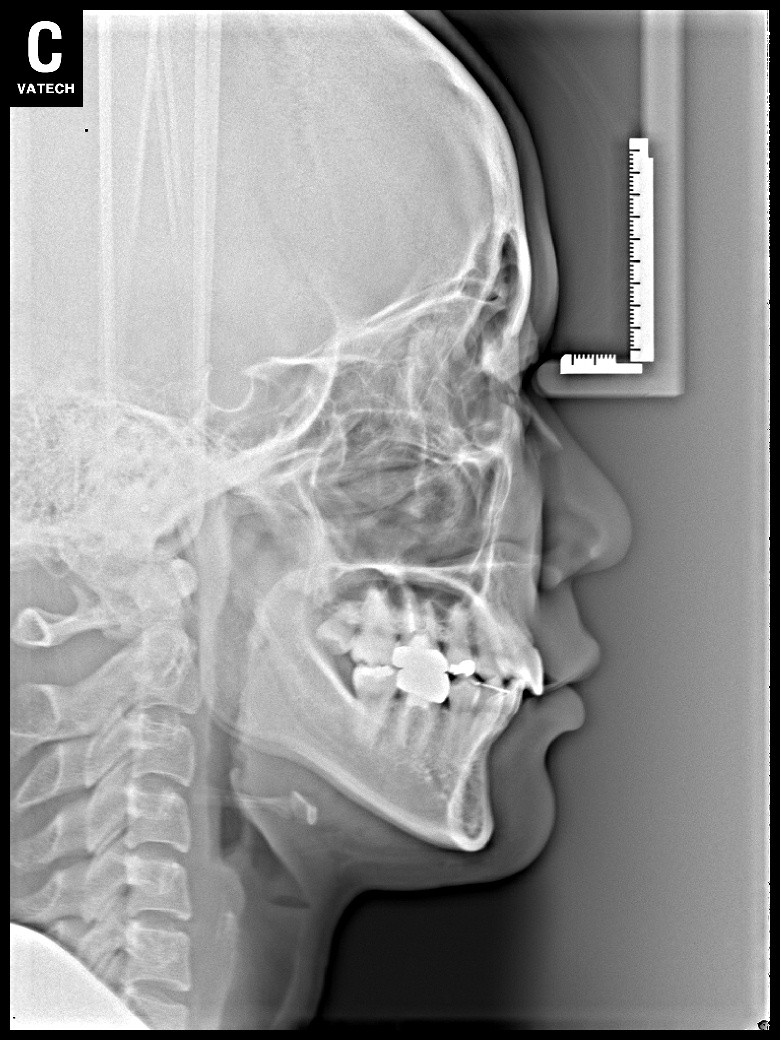

치료 후 사진입니다.